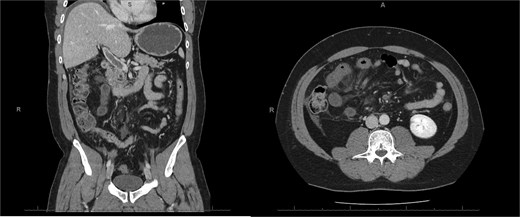

A 76-year-old female with a 3-day history of left upper abdominal pain, vomiting, and haematochezia. Her history included pulmonary embolism, multiple deep vein thromboses, with no ongoing anticoagulation, and an open partial colectomy for complicated diverticulitis a decade earlier. On admission, she was afebrile but tachycardic and showed localized tenderness in the left hypochondrium. Laboratory revealed leucocytosis with a white blood cell count (WBC) of 12 G/L, elevated C-reactive protein (CRP) of 46 mg/L, and hyperlactatemia of 2.6 mmol/l. Enhanced computed tomography (E-CT) revealed jejunal venous ischemia in the left upper quadrant, secondary to extensive porto-mesenteric thrombosis with reduced bowel wall enhancement, distention, and free intraperitoneal fluid (Fig. 1). She was managed conservatively with unfractionated heparin (UFH) with a bolus of 5000 U/l followed by 30 000 U/l/24 h (target INR 0.35–0.7), Piperacillin-Tazobactam, and bowel rest. After 48 h of monitoring in the intensive care unit (ICU), she exhibited marked biological and clinical improvement. E-CT on the third day showed restored bowel wall enhancement and stable porto-mesenteric thrombosis (Fig. 2). She was discharged on therapeutic low molecular weight heparin (LMWH) with enoxaparin sodium 120 mg every 12 h. At the 3-month follow-up, E-CT revealed near-complete thrombus resolution, without intestinal sequelae (Fig. 3).

Abdominal E-CT of the first patient at admission. The white arrows indicate extended porto-mesenteric thrombosis, while the dashed arrows reveal jejunal venous ischemia with a lack of bowel wall enhancement, bowel distension, and free fluid.